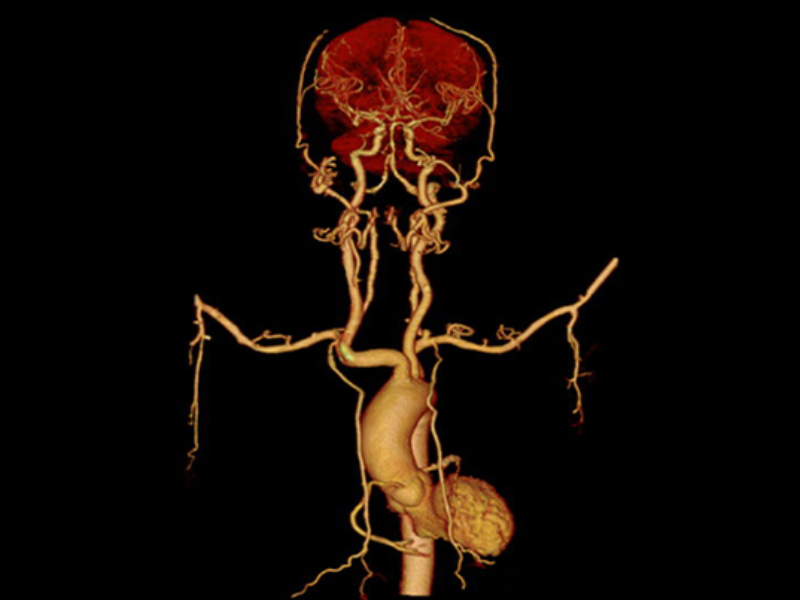

VRT of Abdomen

2 mm MIP